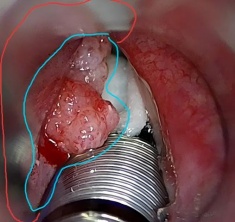

蓝色区域为视野下可见肿瘤,红色区域为视野外肿瘤以及需要切除的范围

为了做到既“精细”又“彻底”,手术团队不断调整支撑喉镜(术野的暴露工具)和显微镜的角度,助手协助按压喉软骨,以配合肿瘤的暴露,逐步辨识出肿瘤的实际范围,努力完整切除了病灶。在不到两指宽的操作空间里,每一次操作都需要耐心和技巧。

为了在彻底切除肿瘤的同时最大可能地保留喉功能,徐赫医生决定实施“显微镜辅助下经直达喉镜喉恶性肿瘤扩大切除术”。显微镜的使用提高了手术难度,但也让肿瘤显露更加清晰。在显微镜的精准鉴别下,肿瘤的实际范围比术前预估的更为广泛。术中取材证实,肿瘤不仅侵犯左侧声带及室带,还累及声带前联合、室带前联合,并牵连至右侧声带及室带前端。即便是微创手术视野,暴露肿瘤的全貌仍存在困难。